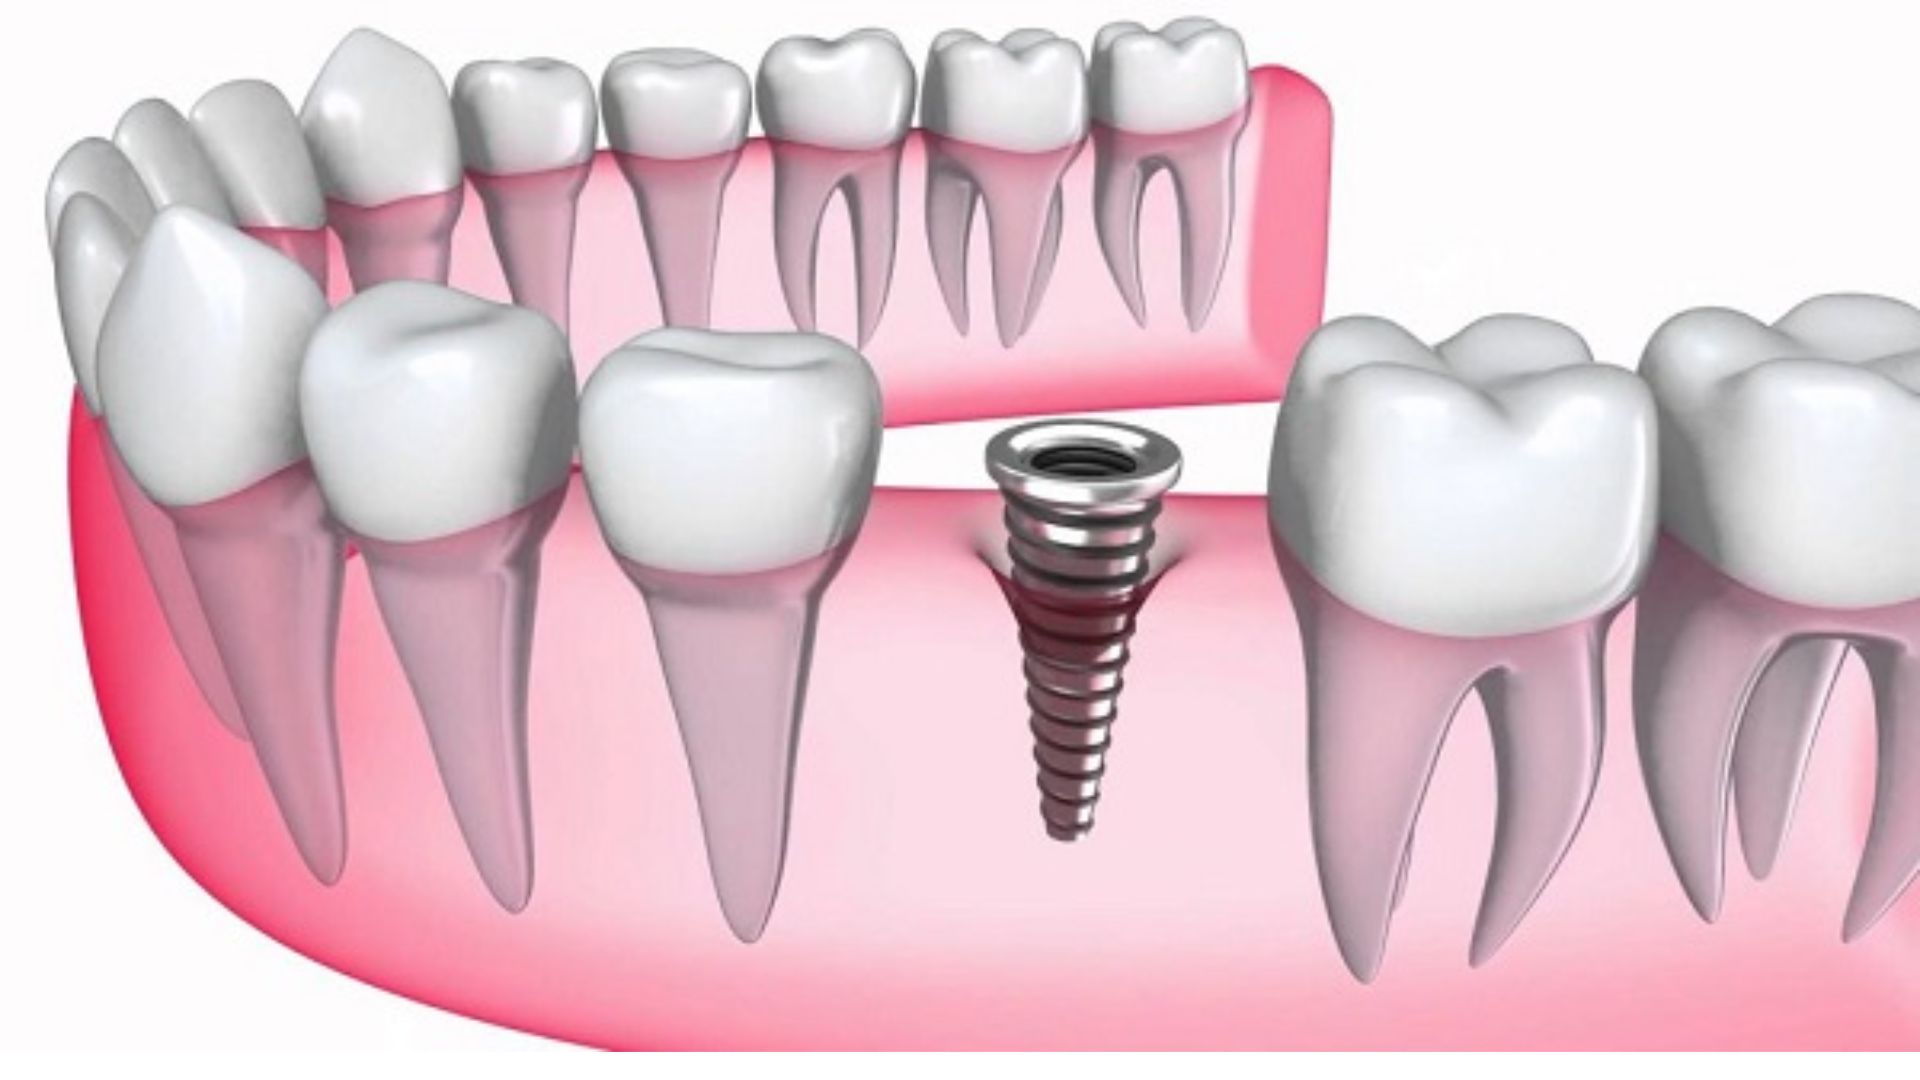

Trồng răng implant hay gọi là cấy ghép implant. Đây là phương pháp phục hồi răng đã mất bằng cách cấy ghép trụ kim loại vào xương hàm tối ưu nhất hiện nay. Làm răng implant có mắc không, có nguy hiểm không? Hãy cùng với BIG DENTAL tìm hiểu về trồng răng implant giá bao nhiêu thông qua bài viết dưới đây.

- Chất liệu titanium cấu tạo nên trụ implant là một chất liệu quý hiếm, được ứng dụng từ lâu trong nha khoa và nhiều ngành công nghệ cao khác như: vỏ phi thuyền, khớp háng nhân tạo, máy bay, …bởi titan nhẹ nhưng cứng và không bị đào thải khi tồn tại thời gian dài trong cơ thể con người.

Trụ Implant đóng một vai trò quan trọng trong quá trình tích hợp xương để sau khi phục hình giúp bạn giữ được trong thời gian dài.

Với sự phát triển của công nghệ trong ngành nha khoa hiện nay, phần trụ Implant được sản xuất theo đúng tiêu chuẩn và hoàn toàn không gây hại với cơ thể. Tùy theo điều kiện kinh tế mà bạn có thể lựa chọn vật liệu cấy ghép Implant phù hợp nhất với bản thân.